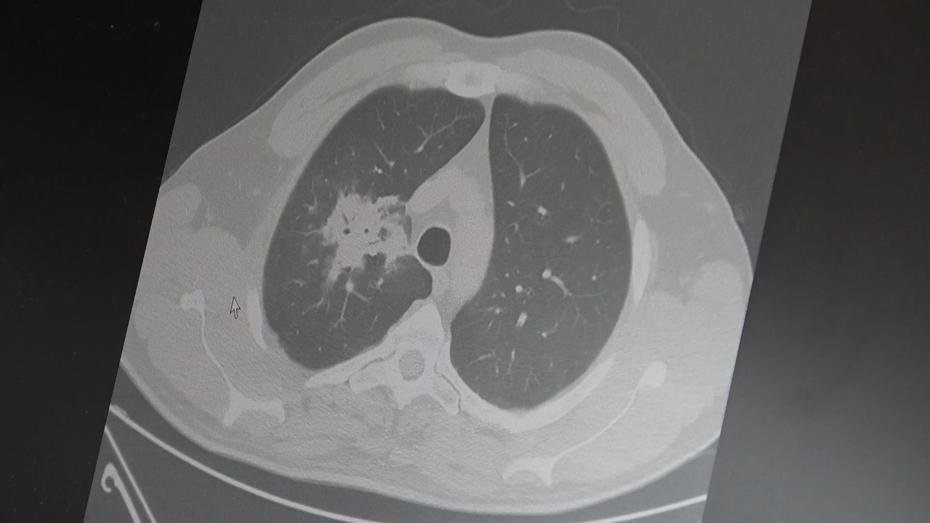

Özkaya, 100’den fazla bilimsel çalışmanın incelendiğini belirterek elektronik sigaraların özellikle akciğer ve ağız bölgelerinde kanser riskini artırabileceğine dair güçlü bulgular bulunduğunu belirtti.

2024 yılında yayımlanan bir çalışmaya da değinen Özkaya, hem geleneksel sigara hem de elektronik sigara kullanan bireylerde akciğer kanseri riskinin, sadece sigara içenlere göre dört kat daha fazla olduğunun bildirildiğini kaydetti.